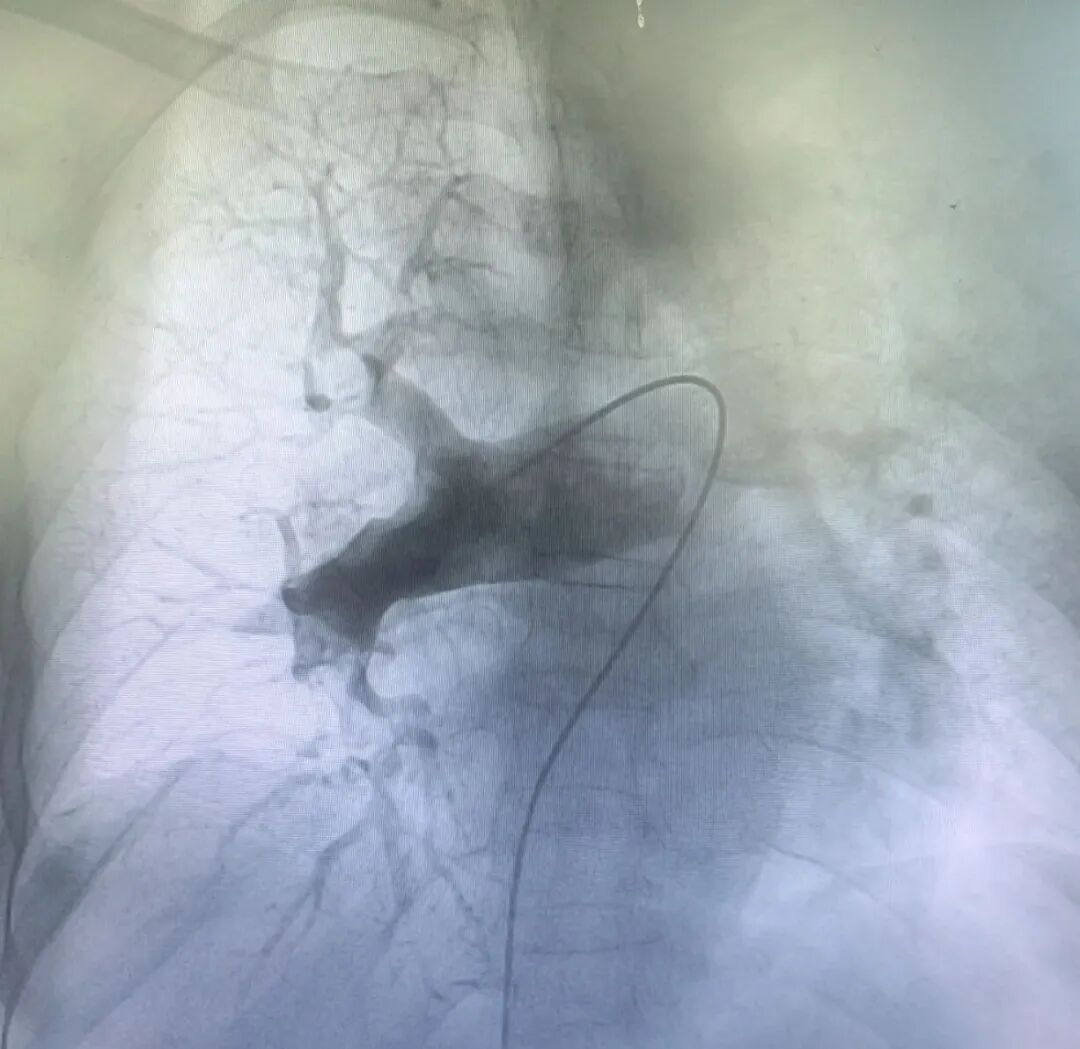

更换置换 22F 血管鞘 , 送入Tendvia®抽栓导管置于右肺动脉血栓近端行血栓抽吸治疗 , 抽取大量红色血栓。将Tendvia®肺动脉取栓支架沿导丝通过抽吸导管向前推送⾄右肺动脉血栓位置,支架头端穿过血栓 ,回撤输送鞘管

,支架自动膨开 ,等待 90 秒 ,连接抽吸器并形成负压 ,回撤取栓支架的同时旋转开关释放负压,血栓由支架收集后进入抽吸导管内

,并在负压抽吸状态下进入抽吸导管中。右肺动脉血栓清除后 ,同样方法清除左侧肺动脉血栓。

复查造影提示左右肺动脉闭塞段复通,血栓负荷明显减少,继续予以后续抗凝治疗。

取栓中

术后造影